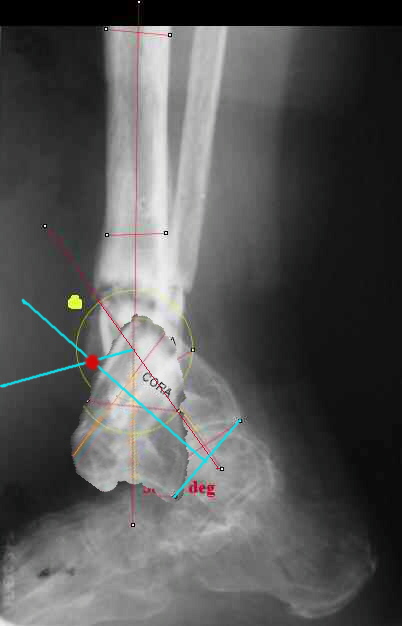

I played with your image using some orthopedic software we have been developing for digital

image analysis.

What you see marked up is the intercept of two mid-line tool centre lines, used to define the CORA. An angle tool gives the angular deformity and a circle tool is applied to show that a correction around the CORA through the old # will restore alignment without much translation.

Maybe my "embedded software" is obsolete but it hints me to place hinges at the yellow point - this must result with alignment and some lengthening without translation. What do you think?

I looked at your image. I presume your yellow marker is the hinge axis? I think this should be at the CORA.